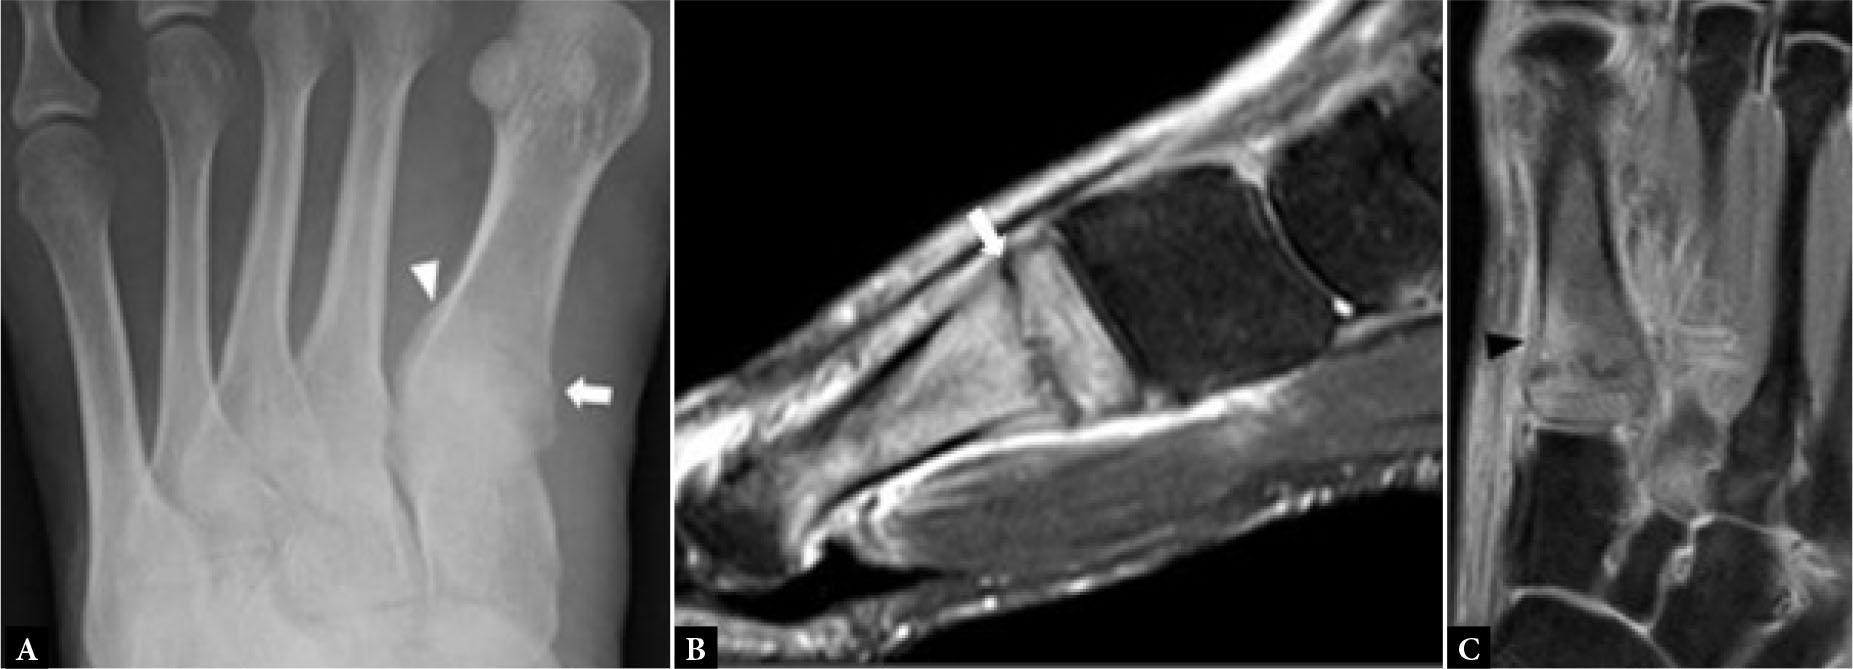

16-year-old female with recent pain plantar aspect 1st MTP joint following a gymnastics tournament. A. Dorsoplantar radiograph of 1st MTP joint shows irregular transverse fracture medial sesamoid bone (open arrow). B. For comparison, on a dorsoplantar radiograph of the contralateral, asymptomatic 1st MTP joint, the medial sesamoid bone is normal (arrow)

Freiberg’s disease is an infraction that most likely follows a subchondral fracture, leading to progressive flattening and collapse most commonly of the second metatarsal head, though the other lesser metatarsal heads may also be affected (Fig. 5). It is about five times more common in females. The diagnosis is usually made radiographically and supported, if necessary, by CT or MRI as a prelude to osteotomy(5). US may potentially help in detecting Freiberg’s disease when radiographs are not available with assessment of inflammation, synovial hypertrophy and hyperemia on Doppler imaging, at the 2nd metatarsophalangeal joint. Otherwise, the role of US in Freiberg’s disease is limited.